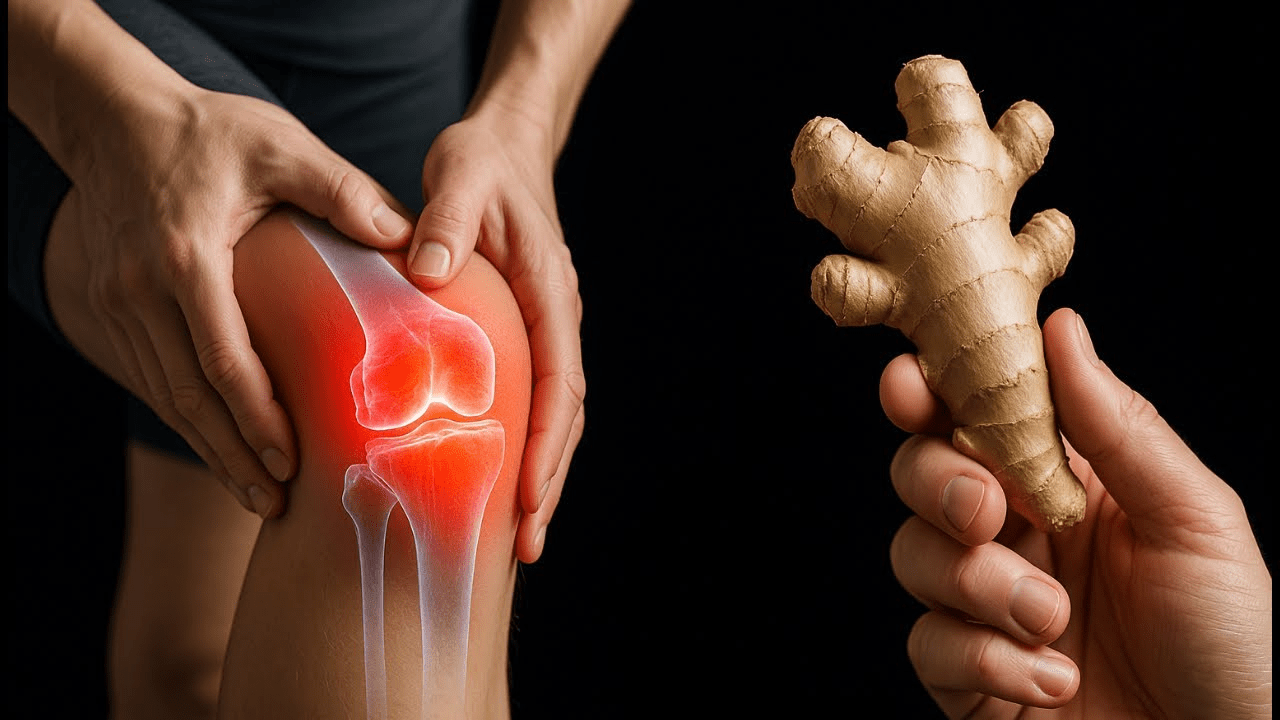

Do your knees ache every time you climb the stairs? Do you hesitate before standing up, dreading that sharp stab or dull throb that follows? You’re not alone — millions of adults wake up each day to the same painful reminder that their joints are wearing down.

For many, knee pain becomes a constant companion, a silent thief stealing their freedom to walk, garden, or even dance without fear. You might have tried painkillers, creams, or supplements, only to find the relief fades as quickly as it came. But what if the key to soothing that pain naturally has been sitting in your kitchen all along?

That’s right — ginger, the golden root once prized in ancient medicine, holds a secret that modern science is only now catching up to. And the best part? You don’t need expensive treatments or synthetic pills to feel its soothing effects.

Let’s explore how this humble spice can help ease stiffness, reduce inflammation, and bring life back to your joints — and how you can start using it today.

Knee pain isn’t just a result of aging. It’s often the product of inflammation — your body’s natural response to stress, injury, or toxins. Over time, that inflammation begins to wear away at cartilage, the cushion that keeps your joints gliding smoothly.

You might notice swelling, warmth, or that dreaded morning stiffness that makes the first few steps unbearable. Painkillers may help temporarily, but they don’t target the root cause — and that’s where ginger steps in.

Ginger isn’t just for cookies or stir-fry. It’s a natural powerhouse packed with bioactive compounds called gingerols and shogaols, which work to calm inflammation and support circulation.

Ancient healers used it to relieve joint pain, muscle soreness, and even fatigue. Today, researchers are finding that ginger’s anti-inflammatory action may mimic — and in some cases enhance — the effects of common pain relievers, without the side effects.

But the real magic lies in its versatility. Whether taken as a tea, applied as a compress, or blended into a warm paste, ginger can support your knees from the inside out.